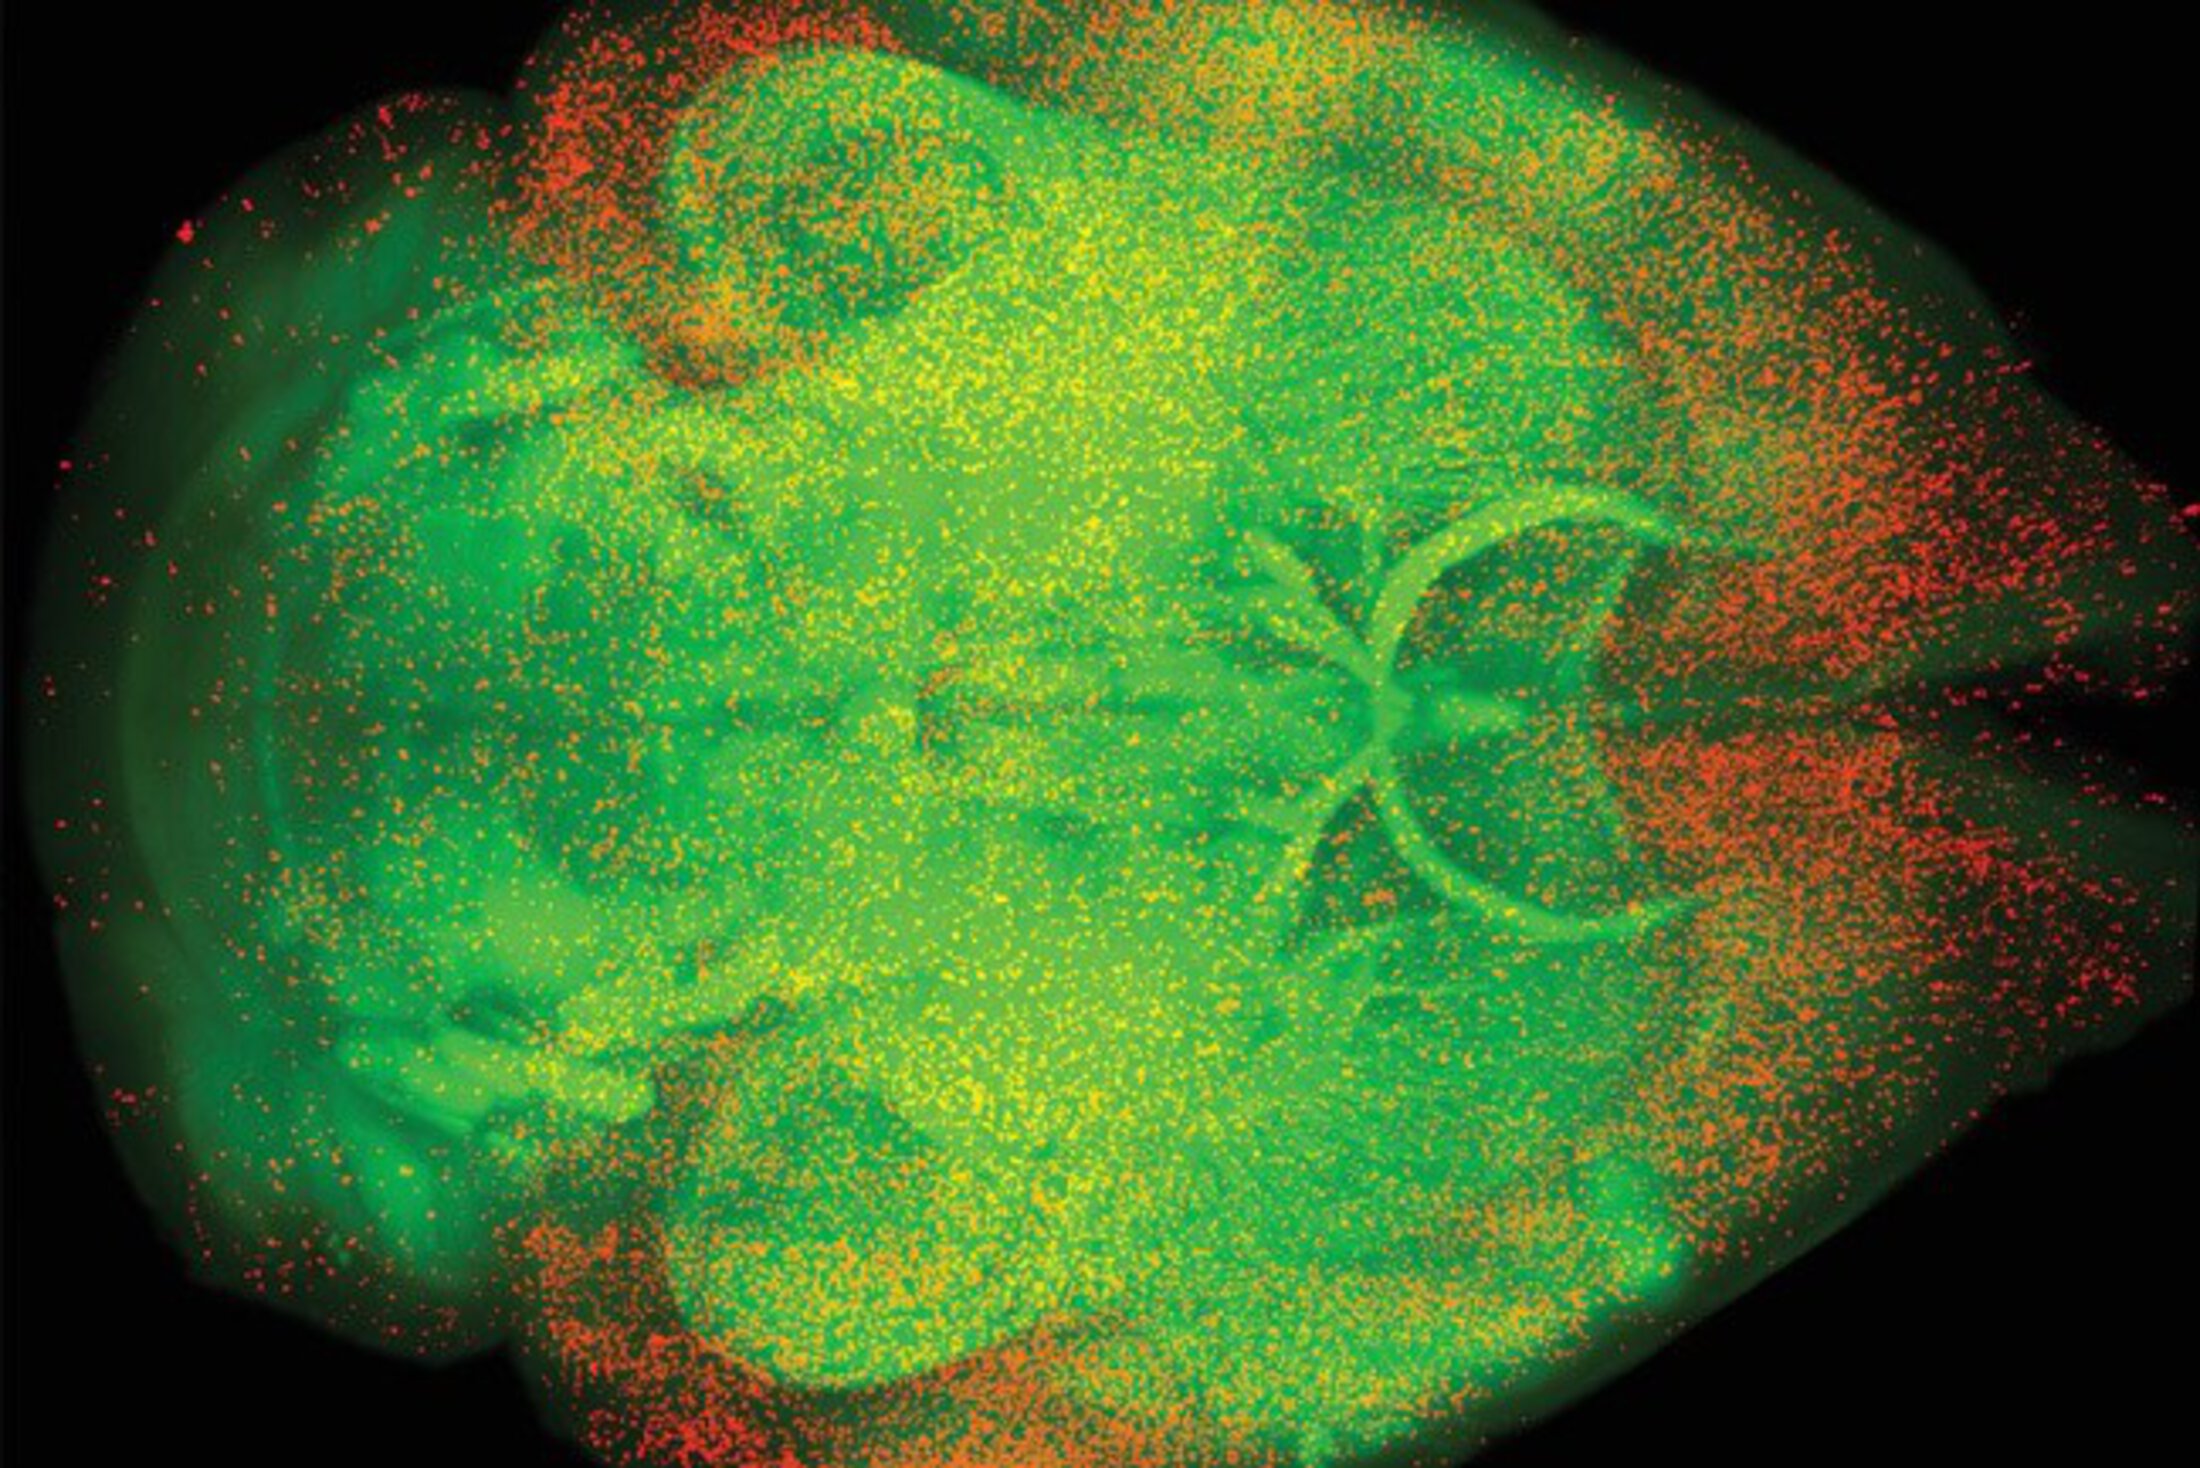

Unbiased whole-brain mapping of c-Fos identifies active brain regions following a rewarding dose of oxycodone. c-Fos-positive cells are shown in red; white matter tracks are shown in green. Credit: Alexander Smith.

In a study published in the June 7 issue of Science, Smith and his team found that an understudied brain region responsible for aversion, the dorsal peduncular nucleus, is highly responsive to opioids. Surprisingly, the opioid receptors in this brain region respond uniquely to opioids, contradicting the prevailing belief that opioids act primarily through dopamine in the brain. This discovery offers an exciting new area of research.

The team, led by Smith and his mentor Paul Kenny, found that mu opioid receptors are abundant on cells in the dorsal peduncular nucleus. The opioid receptors in this region do not result in disinhibition; rather, they are found directly on cells that project to a part of the brain that drives aversive feelings. When opioids bind to these cells, they inhibit them. Removing these aversive feelings leads to reward – a process called negative reinforcement. This contributes to the pleasurable and addictive qualities of opioids.

When Smith got his early results back showing that the dorsal peduncular nucleus was the most significantly affected region by opioids, he had to look up what this brain region did.